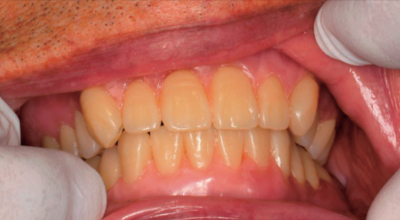

77歳の男性。上顎全部床義歯が外れやすいことを主訴として来院した。検査の結果、上下顎全部床義歯を製作することとした。人工歯排列後に行っている検査中の写真を別に示す。

この過程における確認事項はどれか。2つ選べ。